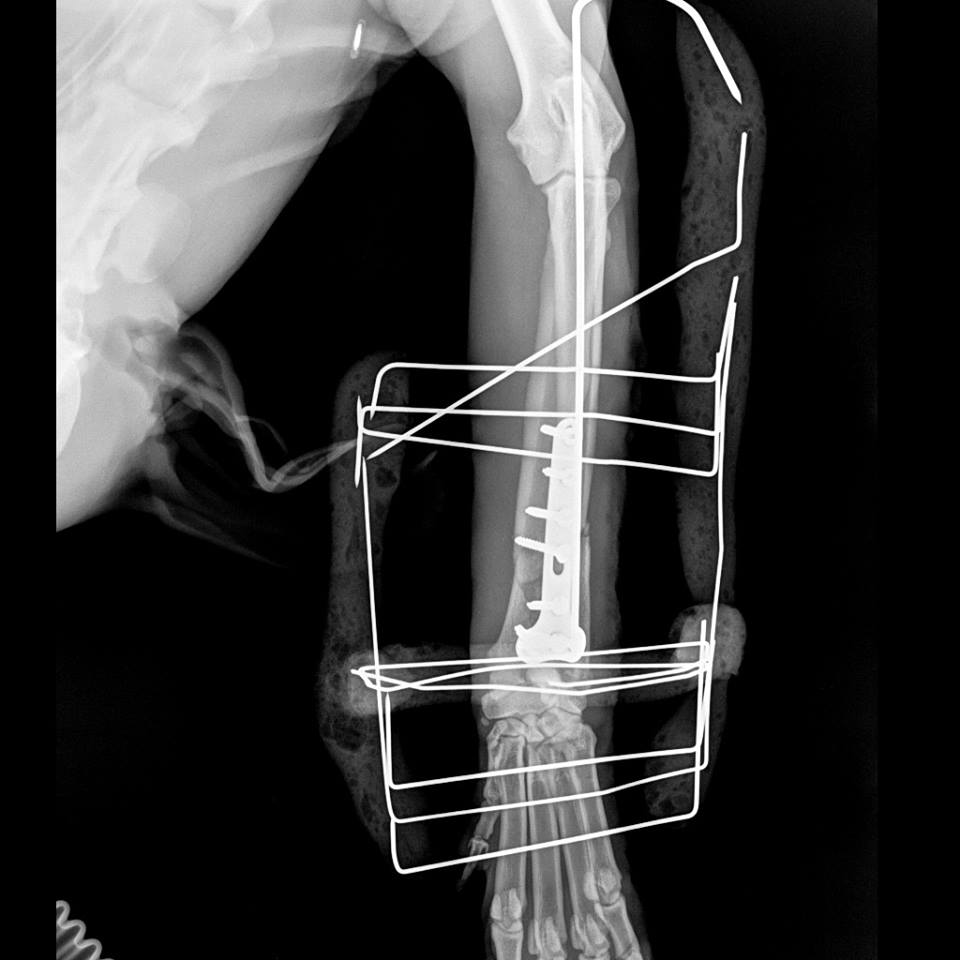

Η κα Μακρή δημοσίευσε σήμερα στο facebook την γνωμάτευση του κτηνιάτρου σχετικά με την εξέλιξη της υγείας του ζώου. Σε αυτή αναφέρεται ότι: «Ο σκύλος έφερε συντριπτικά ενδοαρθρικά κατάγματα με μετατόπιση στο κάτω τρίτο του αριστερού αντιβραχίου και στο κάτω τρίτο του αριστερού μηριαίου. Ολοκληρώθηκε με επιτυχία η πρώτη χειρουργική επέμβαση που αφορούσε την ανάταξη και οστεοσύνθεση του αριστερού αντιβραχίου. Λόγω της σοβαρότητας του κατάγματος η διάρκεια της χειρουργικής επέμβασης ήταν 4 ώρες και 25 λεπτά και ο σκύλος ανένηψε φυσιολογικά».